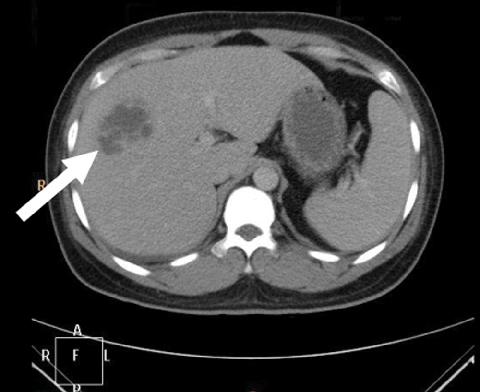

Liver abscess due to Klebsiella pneumoniae infection has been widely reported in Asia, but rarely reported in Australia until now. We describe four previously well Asian-born patients who presented across Australia with community-acquired K. pneumoniae liver abscesses. With prompt recognition, appropriate antibiotics and early drainage, outcome is significantly improved, although vigilance for metastatic complications is essential.

A community-acquired Klebsiella pneumoniae primary invasive liver abscess syndrome has been recognised in Asia for more than 20 years, with almost 1000 reported presentations published by 2008; it has been reported less frequently in other regions.1 K. pneumoniae infection accounted for over 80% of primary liver abscesses reported from Taiwan in the 1990s.2 Increasingly, cases have been seen outside Asia, primarily among patients of Asian ethnicity, including in the United States.1,3 It has only rarely been reported in Australia until now.4,5